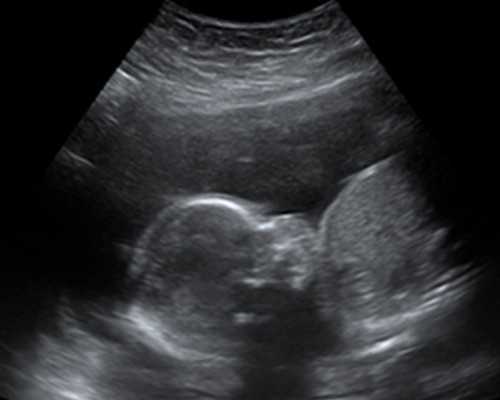

孕期满7周,经过B超检查胎儿胚芽长度达到10mm,能够更准确的检测出胎儿的性别半年之内没有流产过男婴,一年之内没有生过男孩,为了防止母体血液中含有Y染色体,影响胎儿性别的检测

携带港澳通行证和B超单,在预约上之后就需要办理港澳通行证,B超单则是需要和对胎儿周期以及胎儿胚芽长度是否达到10mm,一边检测准确无误。

1、一定要确保宝妈在当地的医院进行B超检测,并且单子上面标注有胚芽长度达到了10mm或者10mm以上,并且宝妈的孕期达到了7周或者7周以上。因为通常只有达到7周才能够进行验血检测。